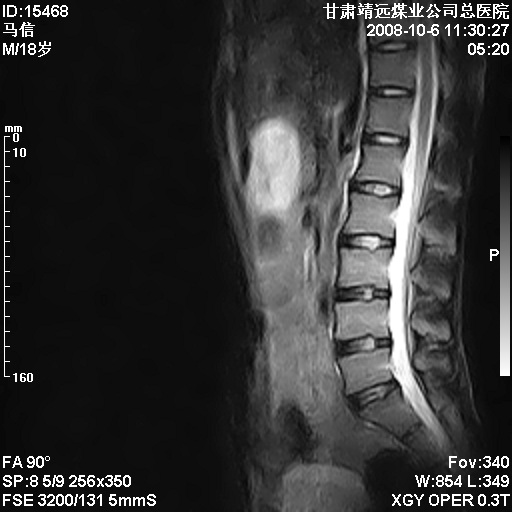

患者18岁,学生,在玩耍中受伤来检查,患者喜欢打篮球。颈椎内异常信号影,我们考虑占位,但是不像占位,又考虑硬膜囊的增厚,大家关建看颈椎椎管内的那个异常占位信号

腰椎的改变是不是正常发育的改变,还是打篮球的长期慢性损伤。

考虑 c3-4 c4-5 c5-6椎间盘突出,l3-4 l4-5 l5-s1椎间盘变性

颈椎建议做增强扫描;腰椎诸椎终板骨骺炎。

后纵韧带增厚,颈2/3、3/4、4/5、5/6椎间盘变性、突出;椎体有旋转,提示椎小关节有问题;腰椎间盘变性,许莫氏结节。

后纵韧带增厚,颈2/3、3/4、4/5、5/6椎间盘变性、突出;椎体有旋转,提示椎小关节有问题。腰椎诸椎体终板骨骺炎可能性大!支持!